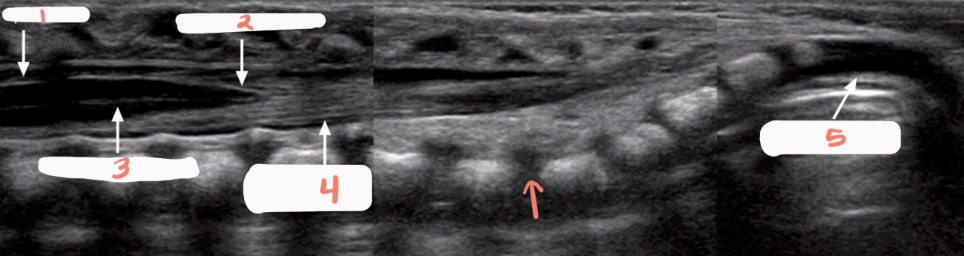

1

spinous processes

2

subarachnoid/dural layer

3

subarachnoid space filled with CSF

4

posterior margin of spinal cord

5

spinal cord with central echo complex

6

anterior margin of the spinal cord

f

filum terminale

c

conus medullaris

a

anterior and posterior margins of spinal cord

b

echogenic nerve roots in the subarachnoid space

what are the calipers measuring?

s

thecal sac

white arrow

end of thecal sac (about s2)

partially calcified coccyx

r

rectum filled with air

hypoechoic spinal cord

arrows

echogenic nerve roots of cauda equina

arrowheads

echogenic dura

*

echogenic vertebral arches

p

spinous process